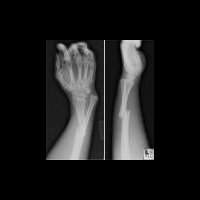

Стволовые клетки помогут в лечении переломов

В экспериментальном исследовании на животных, проведенном американскими биологами, была показана эффективность нового биологического материала при лечении переломов.

Биологический материал-гель, уже получивший неофициальное название «fracture putty», проходит исследования в университете Джорджии в сотрудничестве с исследовательскими группами из университетов Техаса и Райса. В исследовании принимают участие сотрудники медицинского колледжа Бейлора. Выраженное ускорение переломов костей было обнаружено в опытных исследованиях на животных (крысах, свиньях, овцах).

Исследуемый гель вводится непосредственно в место перелома после осуществления остеосинтеза. Гель содержит стволовые клетки мезенхимальной ткани, которые ускоряют образование костной мозоли и заживление ткани.

Крысам требуется 2 недели для клинически значимого заживления перелома, овцам – 4 недели.

Ученые сообщили о проведении заключительного этапа экспериментов на животных в течение ближайших 6 месяцев. Начиная с лета 2012 года, запланированы первые клинические исследования геля. Профессор Стив Стайс считает, что гель поможет «поставить на ноги» больных с переломом в течение нескольких дней.